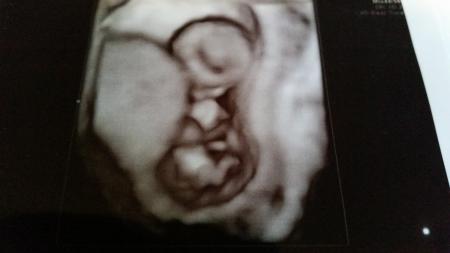

Hier die Bilder vom Ersttrimester Screening und vom letzten FA Besuch.

Bild Nr.3

So jetzt habe ich alle hinzugefügt. Bild 1-3 sind vom Ersttrimesterscreening und die anderen von meiner Ärztin ... Schönen Abend noch Lg Rosi

Schöne Bilder. Toll. da bin ich gespannt auf morgen, vielleicht schaltet mein Gyn bei der NT ja auch mal kurz da 3d Bild dazu. LG